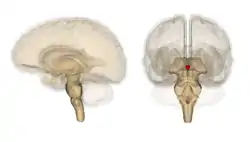

Pineal gland or epiphysis (in red)

Diagram of pituitary and pineal glands in the human brain

The pineal gland (also known as the pineal body,[1] conarium, or epiphysis cerebri) is a small endocrine gland in the brain of most vertebrates. The pineal gland produces melatonin, a serotonin-derived hormone which modulates sleep patterns in both circadian and seasonal cycles. The shape of the gland resembles a pine cone, which gives it its name.[2] The pineal gland is located in the epithalamus, near the center of the brain, between the two hemispheres, tucked in a groove where the two halves of the thalamus join.[3][4] It is one of the neuroendocrine secretory circumventricular organs in which capillaries are mostly permeable to solutes in the blood.[5]

The pineal gland is a pine cone-shaped (hence the name), unpaired midline brain structure.[2][9] It is reddish-gray in colour and about the size of a grain of rice (5–8 mm) in humans. It forms part of the epithalamus.[1] It is attached to the rest of the brain by a pineal stalk.[10] The ventral lamina of the pineal stalk is continuous with the posterior commissure, and its dorsal lamina with the habenular commissure.[10]

It normally lies in a depression between the two superior colliculi.[10] It is situated between the laterally positioned thalamic bodies, and posterior to the habenular commissure. It is located in the quadrigeminal cistern.[1] It is located posterior to the third ventricle and encloses the small, cerebrospinal fluid-filled pineal recess of the third ventricle which projects into the stalk of the gland.[11]